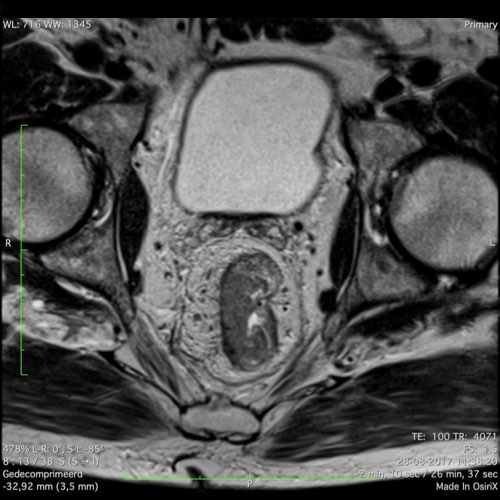

Hình ảnh

Các hình ảnh được cung cấp cho thấy ung thư biểu mô tế bào nhẫn với tình trạng dày lan tỏa thành trực tràng, hình ảnh bia bắn điển hình, và sự xâm lấn mỡ mạc treo trực tràng.